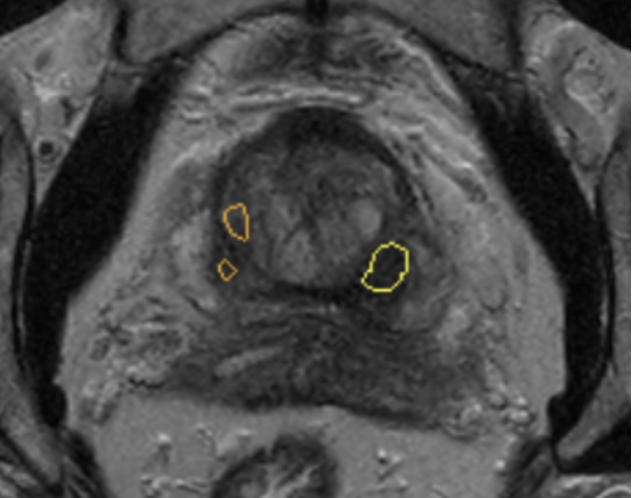

Quibim’s flagship product, QP-Prostate®, is the result of years of research in computer vision. By using biopsy results as ground truth for training and validation, QP-Prostate® identifies and highlights suspicious lesions on prostate, enhancing radiologists’ accuracy and efficiency.

The software provides radiologists with a visual representation of the lesion, and a degree of certainty on the software’s prediction when determining if a lesion could be csPCa.

suspicious lesion on prostate

QP-Prostate®’s results are integrated with the radiologists PACS to ensure minimal disruption to their clinical workflow.

By providing radiologists with an objective estimation, QP-Prostate® aims to improve their diagnostic accuracy (reducing the number of missed cancers, as well as reducing the number of unnecessary biopsies), as well as their reporting time.